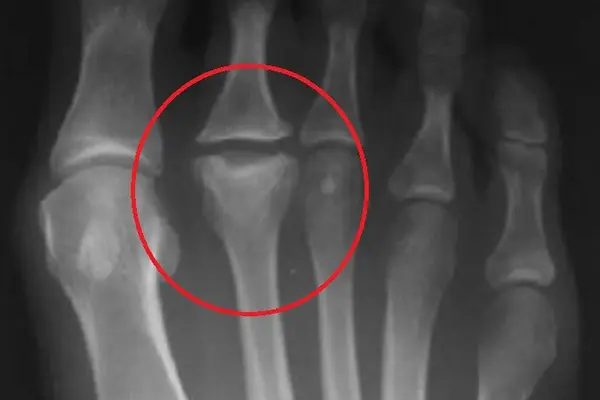

Freiberg Disease, also known as Freiberg Infraction, is a rare but painful condition that affects the metatarsal head (usually the second toe). It occurs when the blood supply to the bone is disrupted, leading to collapse, pain, and stiffness in the toe joint. Over time, patients may experience swelling, difficulty walking, and problems wearing shoes.

What is Freiberg Disease?

Freiberg Disease is a type of osteonecrosis of the metatarsal head, where bone tissue dies due to lack of blood supply. This leads to joint collapse and progressive arthritis in the forefoot. Symptoms include: